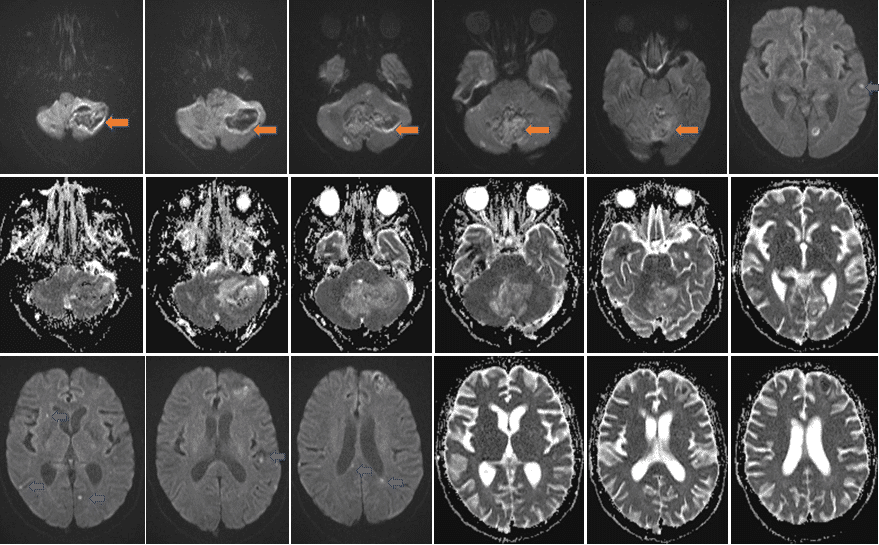

头MR(2023-11-06上图为DWI及ADC序列)双侧小脑、蚓部及左侧额叶不规则片状混杂信号;双侧颞叶、左侧枕叶及胼胝体压部可见弥散信号增高。